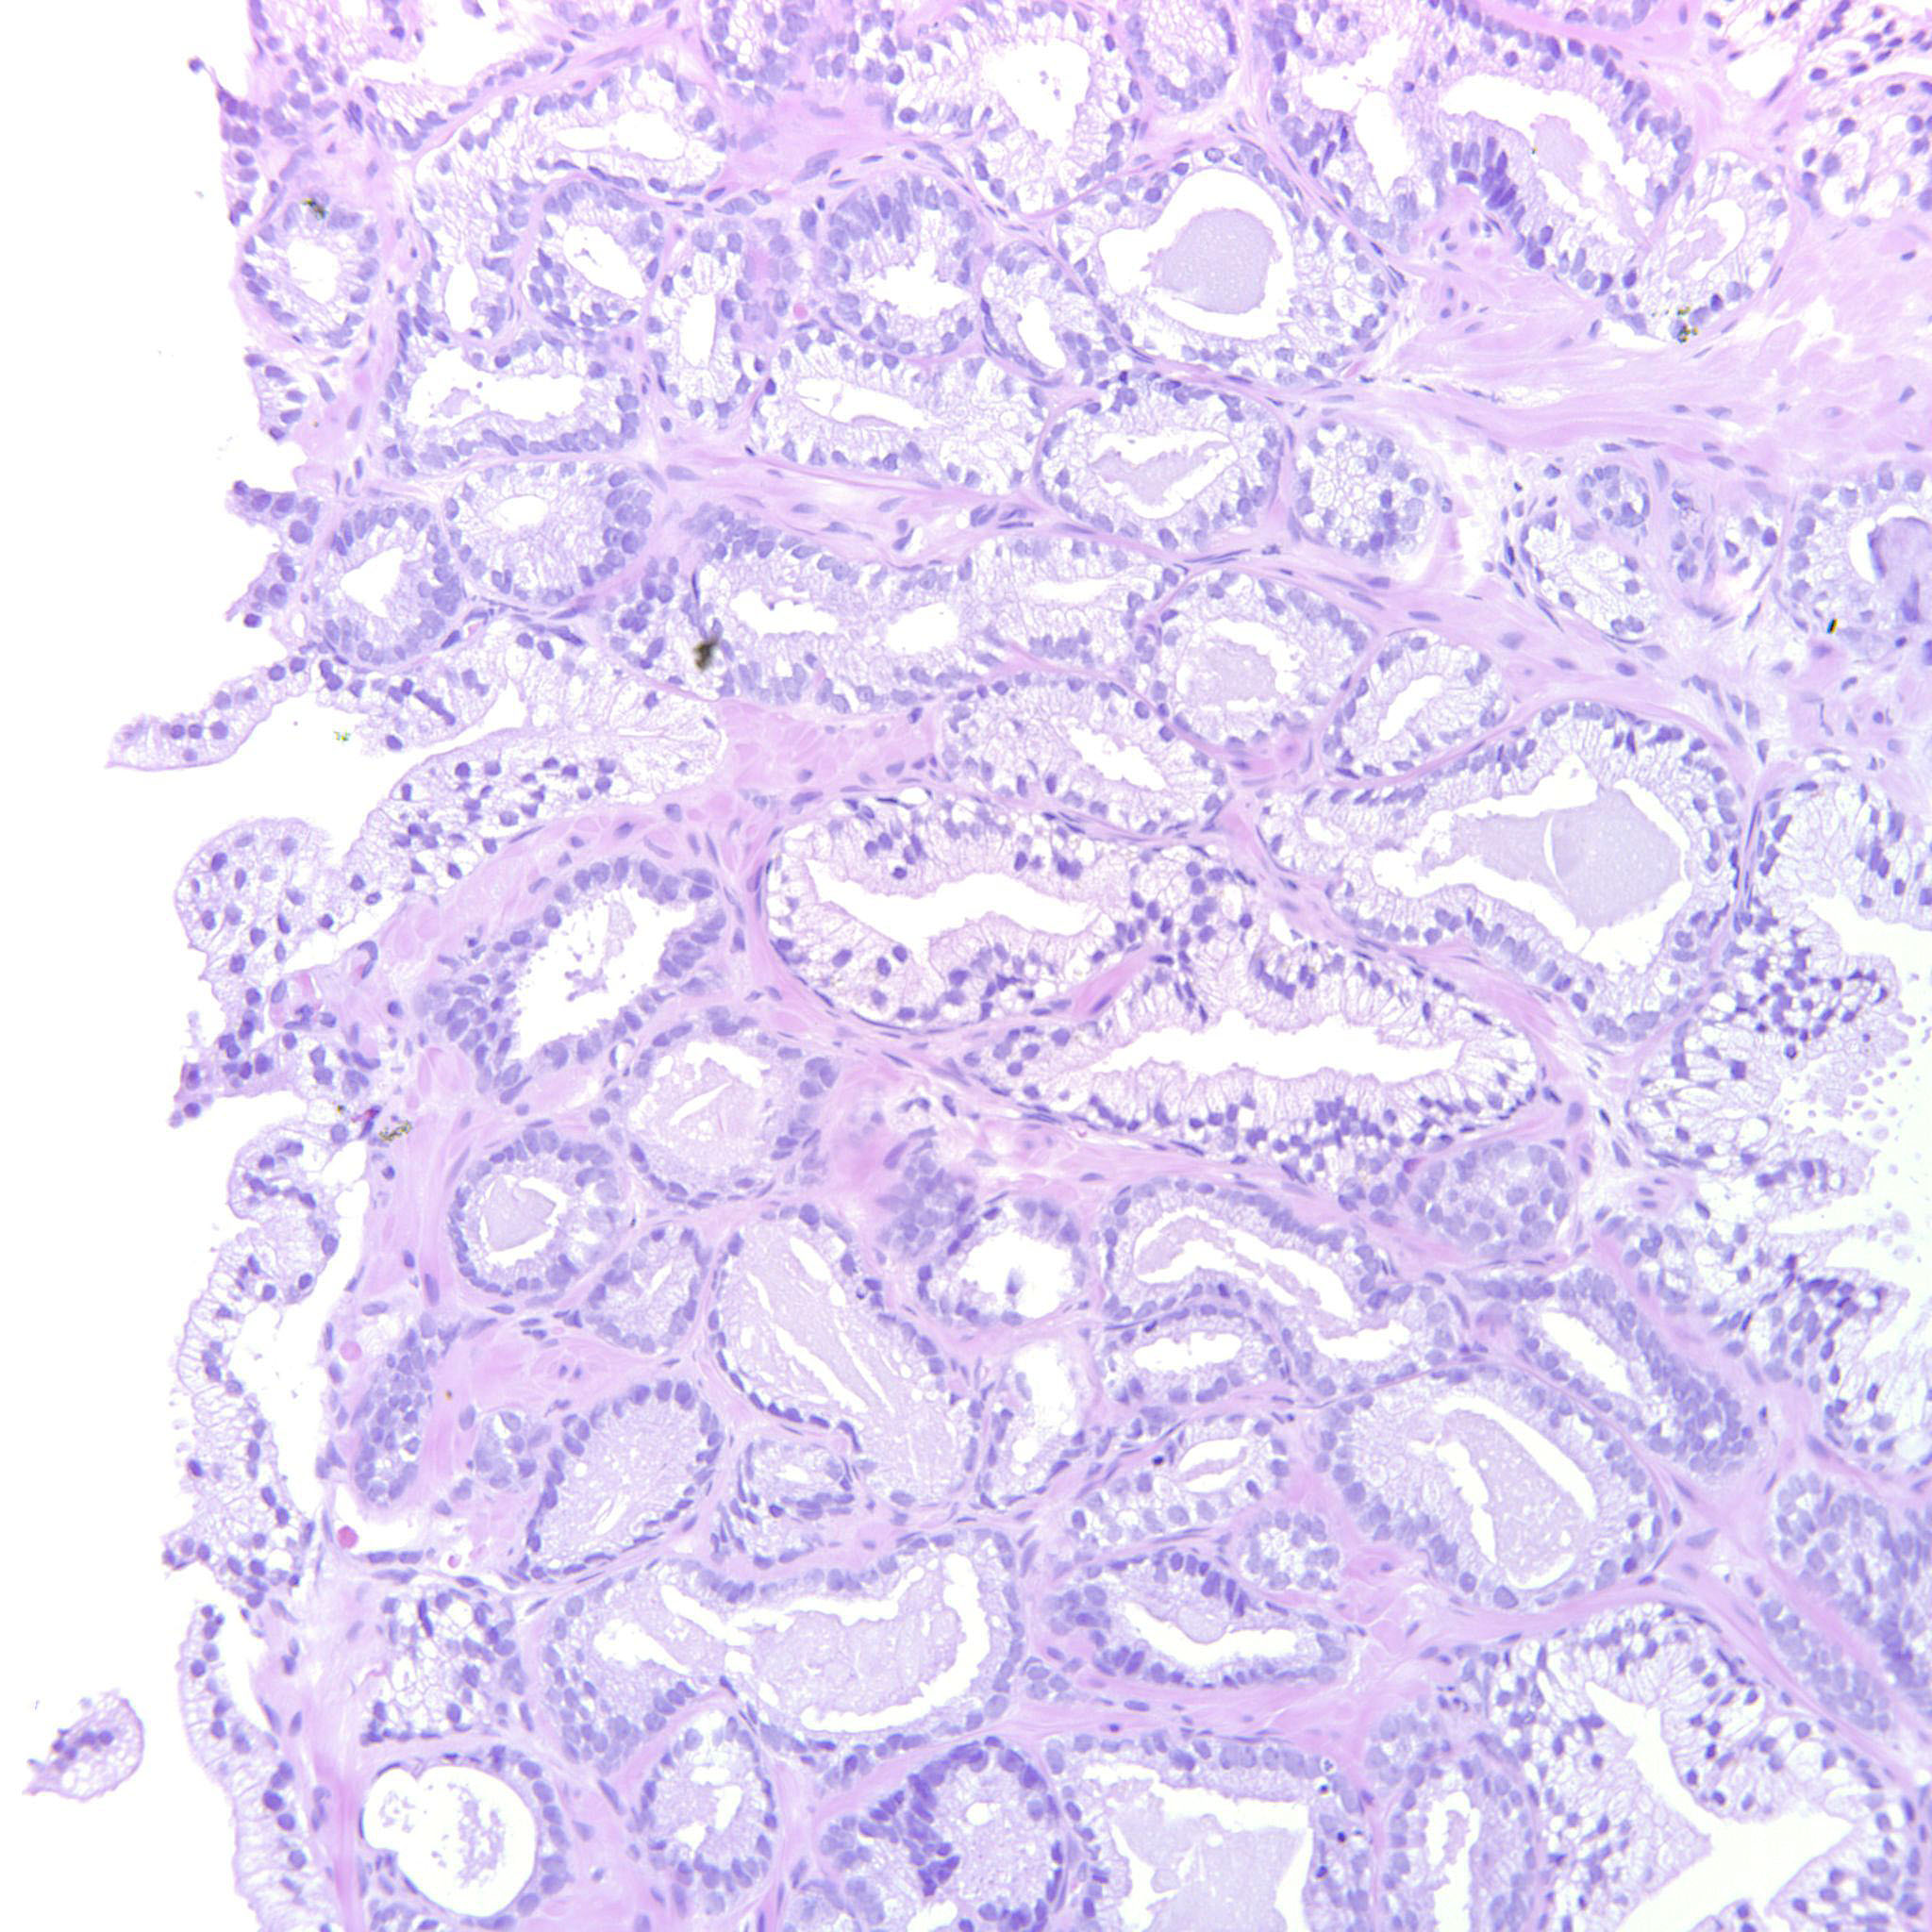

Prostate cancer grading

Case ID: 255

GS 3+3=6 (ISUP 1)

GS 3+4=7 (ISUP 2)

GS 4+3=7 (ISUP 3)

GS 4+4=8 (ISUP 4)

GS 9-10 (ISUP 5)